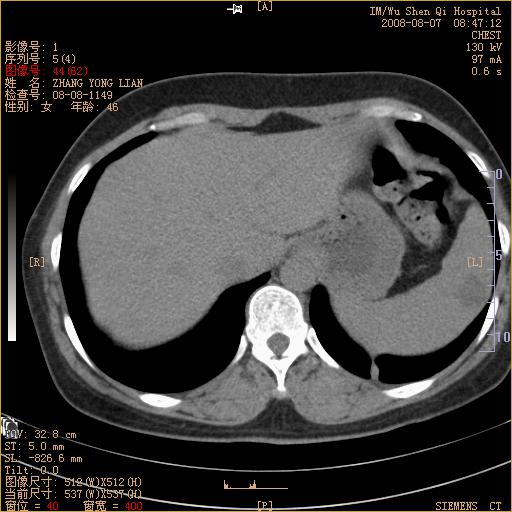

标题: CT15050:女,46岁,咳嗽胸痛一月余 [打印本页]

纵隔窗没发全,左下肺近胸膜处结节。有长毛刺,纵隔淋巴结增大,不排除恶性病变。

考虑左肺下叶后基底段周围型肺癌伴纵隔淋巴结转移可能性大。

左下肺ca并纵隔及左肺门区淋巴结转移。

脾脏低密度结节转移不排除。

1)考虑左肺下叶后基底段周围型肺癌伴纵隔淋巴结转移。2)脾内低密度灶,性质待定;不排除转移瘤可能。

考虑左肺下叶后基底段周围型肺癌伴纵隔及肺门淋巴转移。